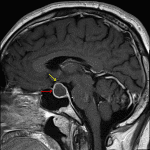

- Peripherally-enhancing sellar/suprasellar mass measuring 2.5 x 1.6 x 1.7 cm, which is not separable from the pituitary gland

- Centrally, the lesion is mildly T1 hypointense and T2 hyperintense

- The lesion bulges to the intercarotid line on the right and remains medial to the medial carotid tangent line on the left

- The lesion contacts and mildly uplifts the optic chiasm

Cystic pituitary adenoma